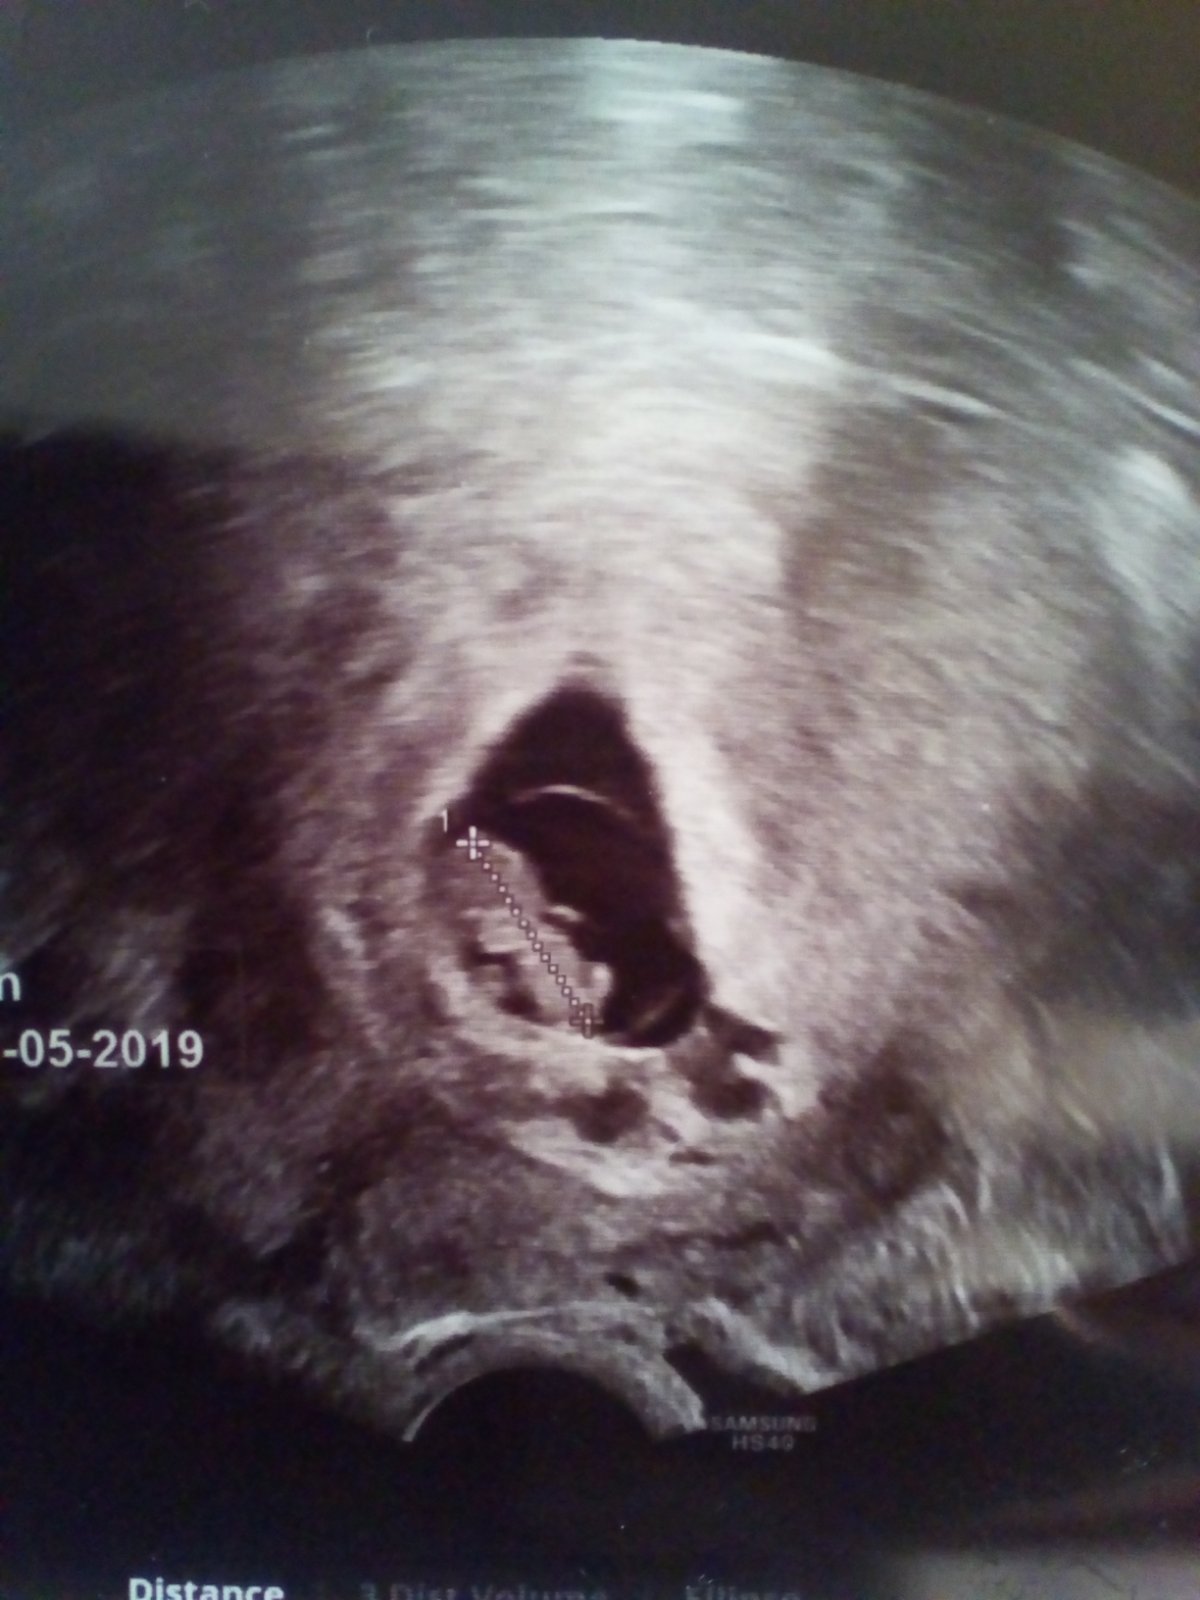

Tak první kontrola zamnou,medvídek odpovídá ovulaci dokonce o den starší 8+0,zítra objednání na screening a před ním u mě Dr kontrolní utz